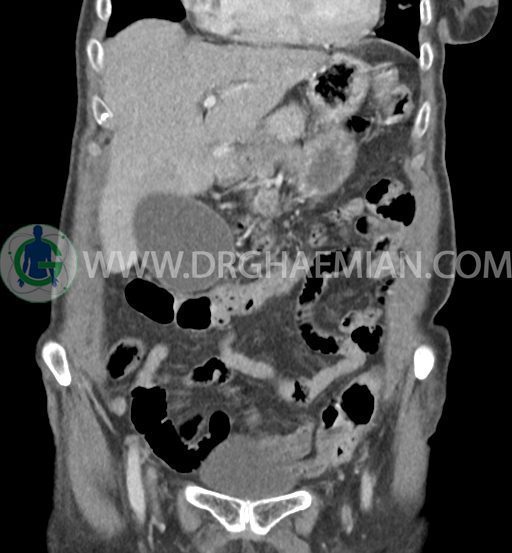

سی تی اسکن شکم و لگن با استفاده از اشعات ایکس تصاویر عرضی از ناحیه شکم و لگن ایجاد میکند. در این کیس سرطان مجرای صفراوی (کولانژیوکارسینوما)، توده در کبد، کیست کورتیکال در کلیه چپ، کلسیفیکاسیون دیواره آئورت و … دیده می شود.

در سی تی اسکن اسپیرال شکم و لگن با و بدون کنتراست خوراکی و وریدی (مولتی دیدکتور 16 با مقاطع ظریف و بازسازی های ساژیتال و کرونال) :

تصویر توده اندکی هیپودنس (HU=40 ) به ابعاد 30x40mm در سگمان 4b کبد ، با حدود ناواضح با enhancement هتروژن و قابل توجه پس از تزریق کنتراست ( HU=70 )، با شواهد تهاجم به گردن کیسه صفرا

تصویر شبیه به توده به قطر 15mm بین خم کبدی کولون و سگمان 6 کبد و قطب تحتانی کلیه راست و به قطر 8mm در انتریور سکوم مطرح کننده توده های peritoneal

کیسه صفرای دیلاته حاوی اسلاژ و سنگ های فراوان به قطر 5mm تا 10mm مطرح کننده کولانژیوکارسینوما

دیلاتاسیون خفیف مجاری صفراوی داخل کبدی

sono guided CNB از توده کبد پیشنهاد می شود .